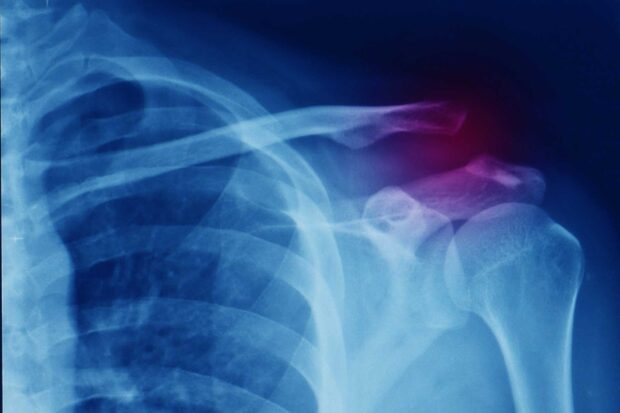

La butée de Latarjet est une technique chirurgicale qui vise à stabiliser les épaules instables. Elle est très efficace comparativement à d’autres techniques. Cette vidéo vous montre en images sa réalisation au bloc opératoire.